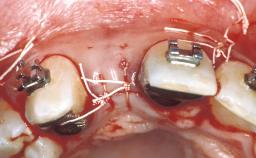

In this video Dr. Nikos Mattheos demonstrates the full diagnostic, planning and treatment sequence of an immediate implant with an immediate prefabricated provisional restoration in the esthetic zone. A 28 years old female patient presents with discoloration and increasing mobility of tooth 11. Advanced stage of external resorption is diagnosed. Patient's high esthetic demands combined with intact gingival architecture and periodontal health makes her a good candidate for immediate placement and restoration to preserve the gingival contour. Surgical and restorative treatment is planned with digital workflow based on data from CBCT and intraoral scan. An immediate temporary crown is manufactured for placement at the day of the surgery. Flapless extraction is performed, and the implant placed with guided surgery. Consequently, the buccal gap of the socket is augmented with Xenograft, while the soft tissue space maintained with a collagen plug. Finally, a provisional crown is immediately placed on the implant with a titanium temporary abutment and an emax prefabricated crown.

Timing of placement Immediate Placement (extraction sockets) (Type I)

Socket walls Intact

Thickness of buccal wall less than 2 mm

Anticipated residual defect after implant placement 2 mm or less